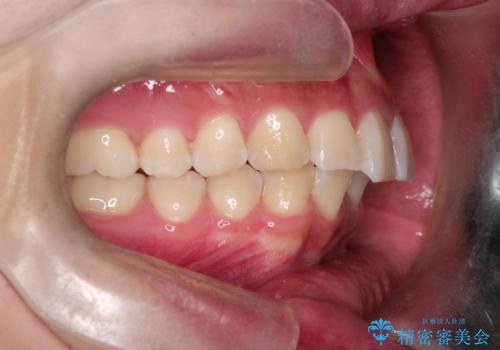

【インビザライン】短期間で出っ歯を治したい

- 出っ歯と口元の突出感が気になるということで来院されました。抜歯矯正も考えられますが、今回は早く終わらせたいという要望があり非抜歯での治療にしました。また遠方から来院されているため、来院回数のおさえられるインビザラインを選択しました。

非抜歯での治療のため、今回はスペース確保のために遠心移動とおもにIPRの処置を取り入れました。